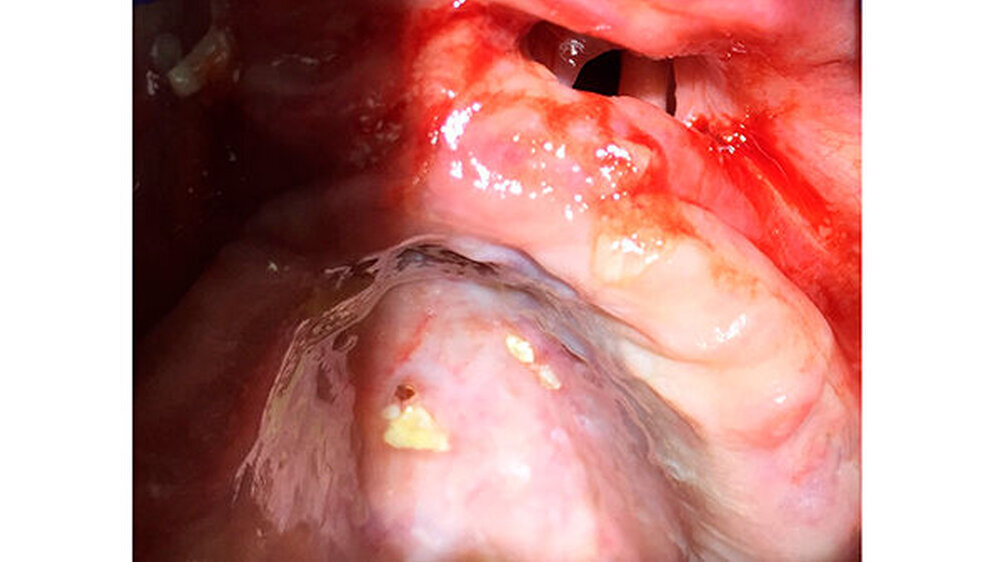

Die Patientin war multimorbide und deshalb zuvor mehrere Wochen stationär behandelt worden. Sie war in einem sehr schlechten Allgemeinzustand, immobil und wurde im Rollstuhl gebracht. Eine Röntgenuntersuchung zeigte keinen Befund, außer einer Überportion Haftcreme unter der Oberkieferprothese. Die Patientin wurde angehalten, diesen Überschuss daheim zu entfernen. Bei ihrem zweiten Besuch kam sie ohne Prothese und die Zahnärztin konnte den Gaumen genauer inspizieren.

Der Gaumen war perforiert, was den anfänglichen Verdacht einer Mund-Antrum-Verbindung (MAV) bestätigte. Mit dem Verdacht auf eine Wegner`sche Granulomatose überwies die Zahnärztin die Patientin zum Internisten, der in der Blutuntersuchung jedoch nur leicht erhöhte ANA- und ANCA-Werte feststellen konnte, die den Verdacht auf eine Autoimmunerkrankung nicht bestätigten.

Dieser Fall zeigt deutlich, wie wichtig es ist, dass das Klinik- und Pflegepersonal umfassend geschult ist, wie eine Prothese richtig und vor allem regelmäßig zu reinigen und zu kontrollieren ist. Hier hatte der nicht mehr passende Zahnersatz zu massiven Druckstellen geführt, was sich schließlich in einer deutlichen Gewebedestruktion zeigte.